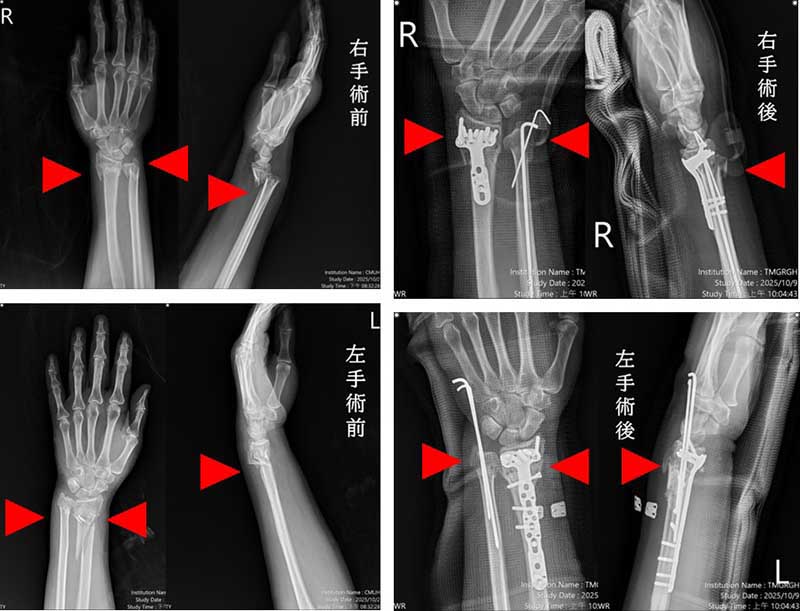

一名57歲婦人因交通事故導致雙手多處骨折與脫位,經本院急診救治,診斷為粉碎性複雜性骨折,本院啟動「多主治醫師協同手術機制」,由骨科部蘇伯翰、江晟弘、毛睿廷三位主治醫師同步進行左右手微創手術,僅一小時即完成四處骨折修復,術後三日順利出院。此創新機制將傳統五小時的手術時間縮短為一小時,大幅減少疼痛與麻醉副作用,並降低醫療人力負擔。

蘇伯翰醫師指出,該名傷患送至本院急診後,即時進行復位與石膏固定,並於24小時內安排開刀,採用「多主治協同手術模式」,由三位主治醫師同時操作左右手四處骨折微創手術,縮短手術時間至約一小時,協同分工可加快病患恢復速度,並提升安全性。患者傷口小、出血少,隔天即可開始復健,三天後平安出院,恢復良好。